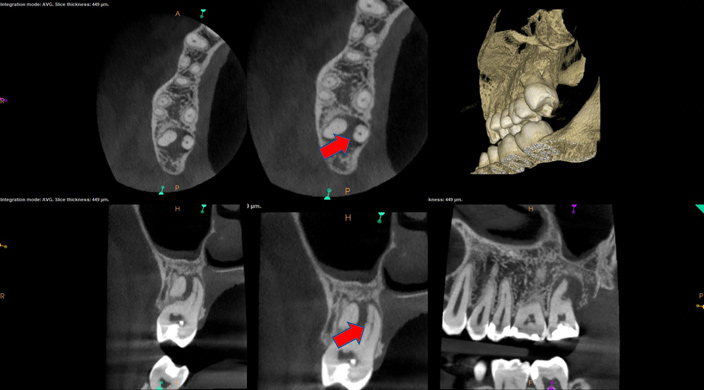

The second case study is that of a healthy 88-year-old woman who presented with significant bone loss on the mesial and apical aspect of tooth No. 18, which would suggest potentially a vertical fracture in the tooth (Figure 9 and Figure 10). The clinician had initially recommended extraction, which they informed the patient would likely be the best course of action, especially given that she had plenty of bone anterior to the tooth to place implants. When the recommendation of extraction was made to the referring dentist, he had some resistance because both he and the patient were interested in saving the tooth. Although the clinician initially stood firm on the recommendation, he received a call from the general dentist about a month later. He further expressed their desire to save the tooth, and he asked if the endodontist thought the new technology, the GentleWave Procedure, could be a solution. The informed consent was obtained and the patient was scheduled for treatment. Because the canal was quite calcified apically, a defined working length could not be determined. Obturation was performed using warm vertical condensation of gutta-percha.

As indicated in Figure 11, the mesial aspect of the distal canal was never touched by instruments, yet he was able to clean, evidenced by the postoperative image. In the past, a case with this level of difficulty would have required at least two appointments, with an interim medication of calcium hydroxide, but the case was treated in a single-visit appointment.  As observed 7 months later (Figure 12), the patient returned completely asymptomatic, and complete bone healing had occurred that exceeded initial expectations.

Fig 9. Case 2: Significant bone loss on the mesial and apical aspect suggested a potential vertical fracture (Fig 9 and Fig 10). Radiographic images were taken immediately postoperatively (Fig 11) and 7 months postoperatively (Fig 12).

Figure 9

Fig 10. Case 2: Significant bone loss on the mesial and apical aspect suggested a potential vertical fracture (Fig 9 and Fig 10). Radiographic images were taken immediately postoperatively (Fig 11) and 7 months postoperatively (Fig 12).

Figure 10

Fig 11. Case 2: Significant bone loss on the mesial and apical aspect suggested a potential vertical fracture (Fig 9 and Fig 10). Radiographic images were taken immediately postoperatively (Fig 11) and 7 months postoperatively (Fig 12).

Figure 11